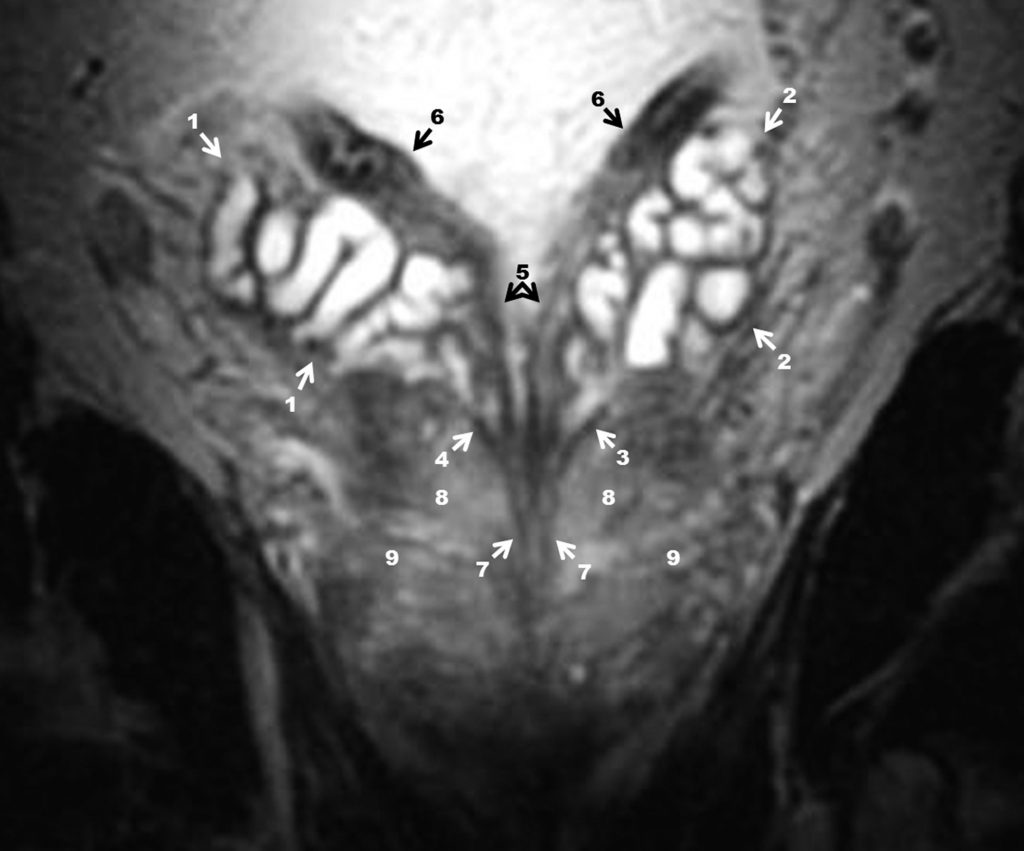

Fig. 19.12. IRM de la prostate : coupe frontale en pondération T2 passant par le confluent vésiculo-déférentiel.

1. Vésicule séminale droite. 2. Vésicule séminale gauche. 3. Conduit excréteur de la vésicule séminale gauche. 4. Conduit excréteur de la vésicule séminale droite. 5. Conduits déférents. 6. Ampoules déférentielles. 7. Conduits éjaculateurs. 8. Zone centrale de la prostate. 9. Zone périphérique (postérieure et latérale).

Source : CERF, CNEBMN, 2022.